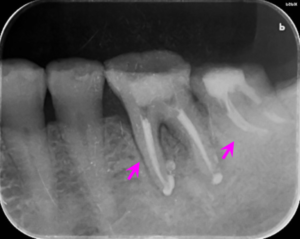

左下の奥歯のレントゲン写真です。

矢印部の骨が炎症にて吸収されていました。

歯ぎしりによる歯の摩耗で細菌の感染を受けて炎症が起こっていました。そのため、歯の根の治療を行いました。

左下の奥歯の根の治療後のレントゲン写真です。

矢印部にみられた骨の吸収像はなくなり、歯ぐきの炎症も改善しました。